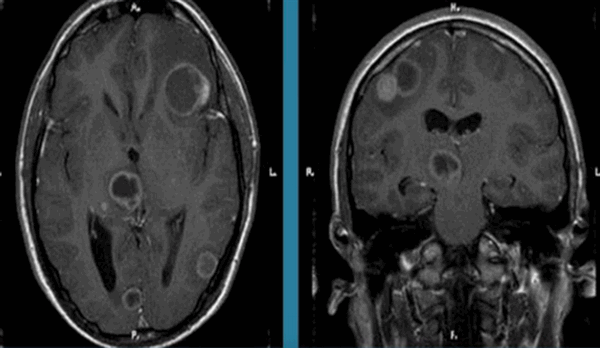

МРТ головного мозга. Т1-взвешенная МРТ с контрастированием. Множественные менингиомы при нейрофиброматозе 2 типа. Цветовая обработка изображения.

Нейрофиброматоз II типа также имеет аутосомно-доминантный тип наследования, но сцепленный с 22 парой хромосом. Его частота составляет один на 100 тыс. населения. Диагностическими критериями служат (National Institutes of Health, 1988) двухсторонние невриномы слуховых нервов, выявляемые на КТ или МРТ, либо сочетание наследственной предрасположенности (наличие двухсторонних неврином у ближайшего родственника) с односторонней невриномой или двумя другими типичными опухолями (плексиформная нейрофиброма, менингиома, глиома, невринома любой локализации) плюс кожные пятна. В отличие от НФ I кожные пятна единичные и не служат главным критерием, а опухолевое поражение ассоциируется не с астроцитомами, а с невриномами и менингиомама. Сопутствующими патологиями являются менингоангиоматоз, глиальные узлы, эпендимальные эктопии, гипертрофический глиоз зрительного нерва, сирингомиелия, комплекс Арнольда-Киари. Типичная невринома развивается из шванновской оболочки слуховых нервов (VIII пара), обычно с обеих сторон , реже тройничного нерва или других. При МРТ невриномы гипо- или изоинтенсивны белому веществу на Т1-взвешенных МРТ и изо- или гиперинтенсивны на Т2-взвешенных МРТ. Хорошо усиливаются гадолинием. Менингиомы, как правило, сопутствуют невриномам. Локализация не отличается от случаев не связанных с нейрофиброматозом, но встречается также нетипичное поражение сосудистого сплетения. Картина менингиом при нейрофиброматозе II типа имеет все типичные признаки.